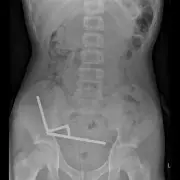

Groundbreaking spinal surgery using a custom 3D-printed titanium vertebra has transformed a young man's life after a devastating motorcycle accident, marking a UK medical milestone.